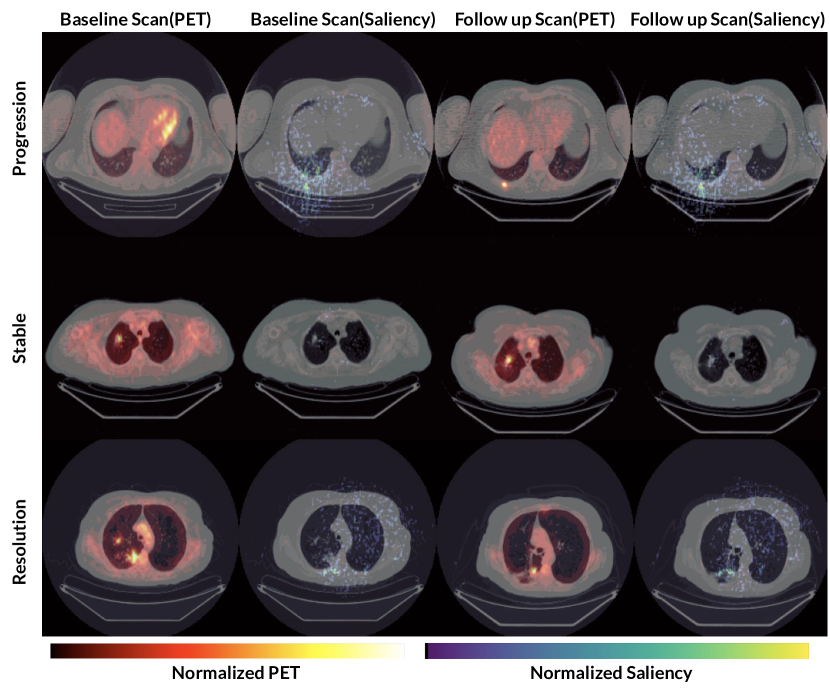

In Figure 3 we produce guided backpropagation saliency maps over each slice of the PET/CT to understand which voxels OncoNet’s classification is most sensitive to. The top row shows an instance of diseases progression where saliency is concentrated on the new tumor in the lower left. The middle row shows a stable tumor nodule. There is no spike in saliency on the stable tumor suggesting that the model is not focused on solely abnormality detection but change in abnormality. Finally, in the bottom row we see that when there is a reduction in the disease from the previous scan, the saliency identifies the region where tumor was resolved.

Figure 3: Examples of Saliency Maps produced by OncoNet on true positives from the test set. The first and third column visualize the PET overlayed on the CT for the baseline and follow up scans. The second and the fourth column visualize the saliencies overlayed on the CT for the baseline and follow up. The top row shows the emergence of a new tumor (progression) in the bottom left part of the scan and the saliency focuses on the region of the change. In the middle row, the same tumor is seen across both scans indicating stable disease. The saliency is faint given that OncoNet focuses on change in disease and not the presence/absence of disease. In the bottom row the tumor present in the baseline regresses and the saliency focuses on the region where the tumor reduced.